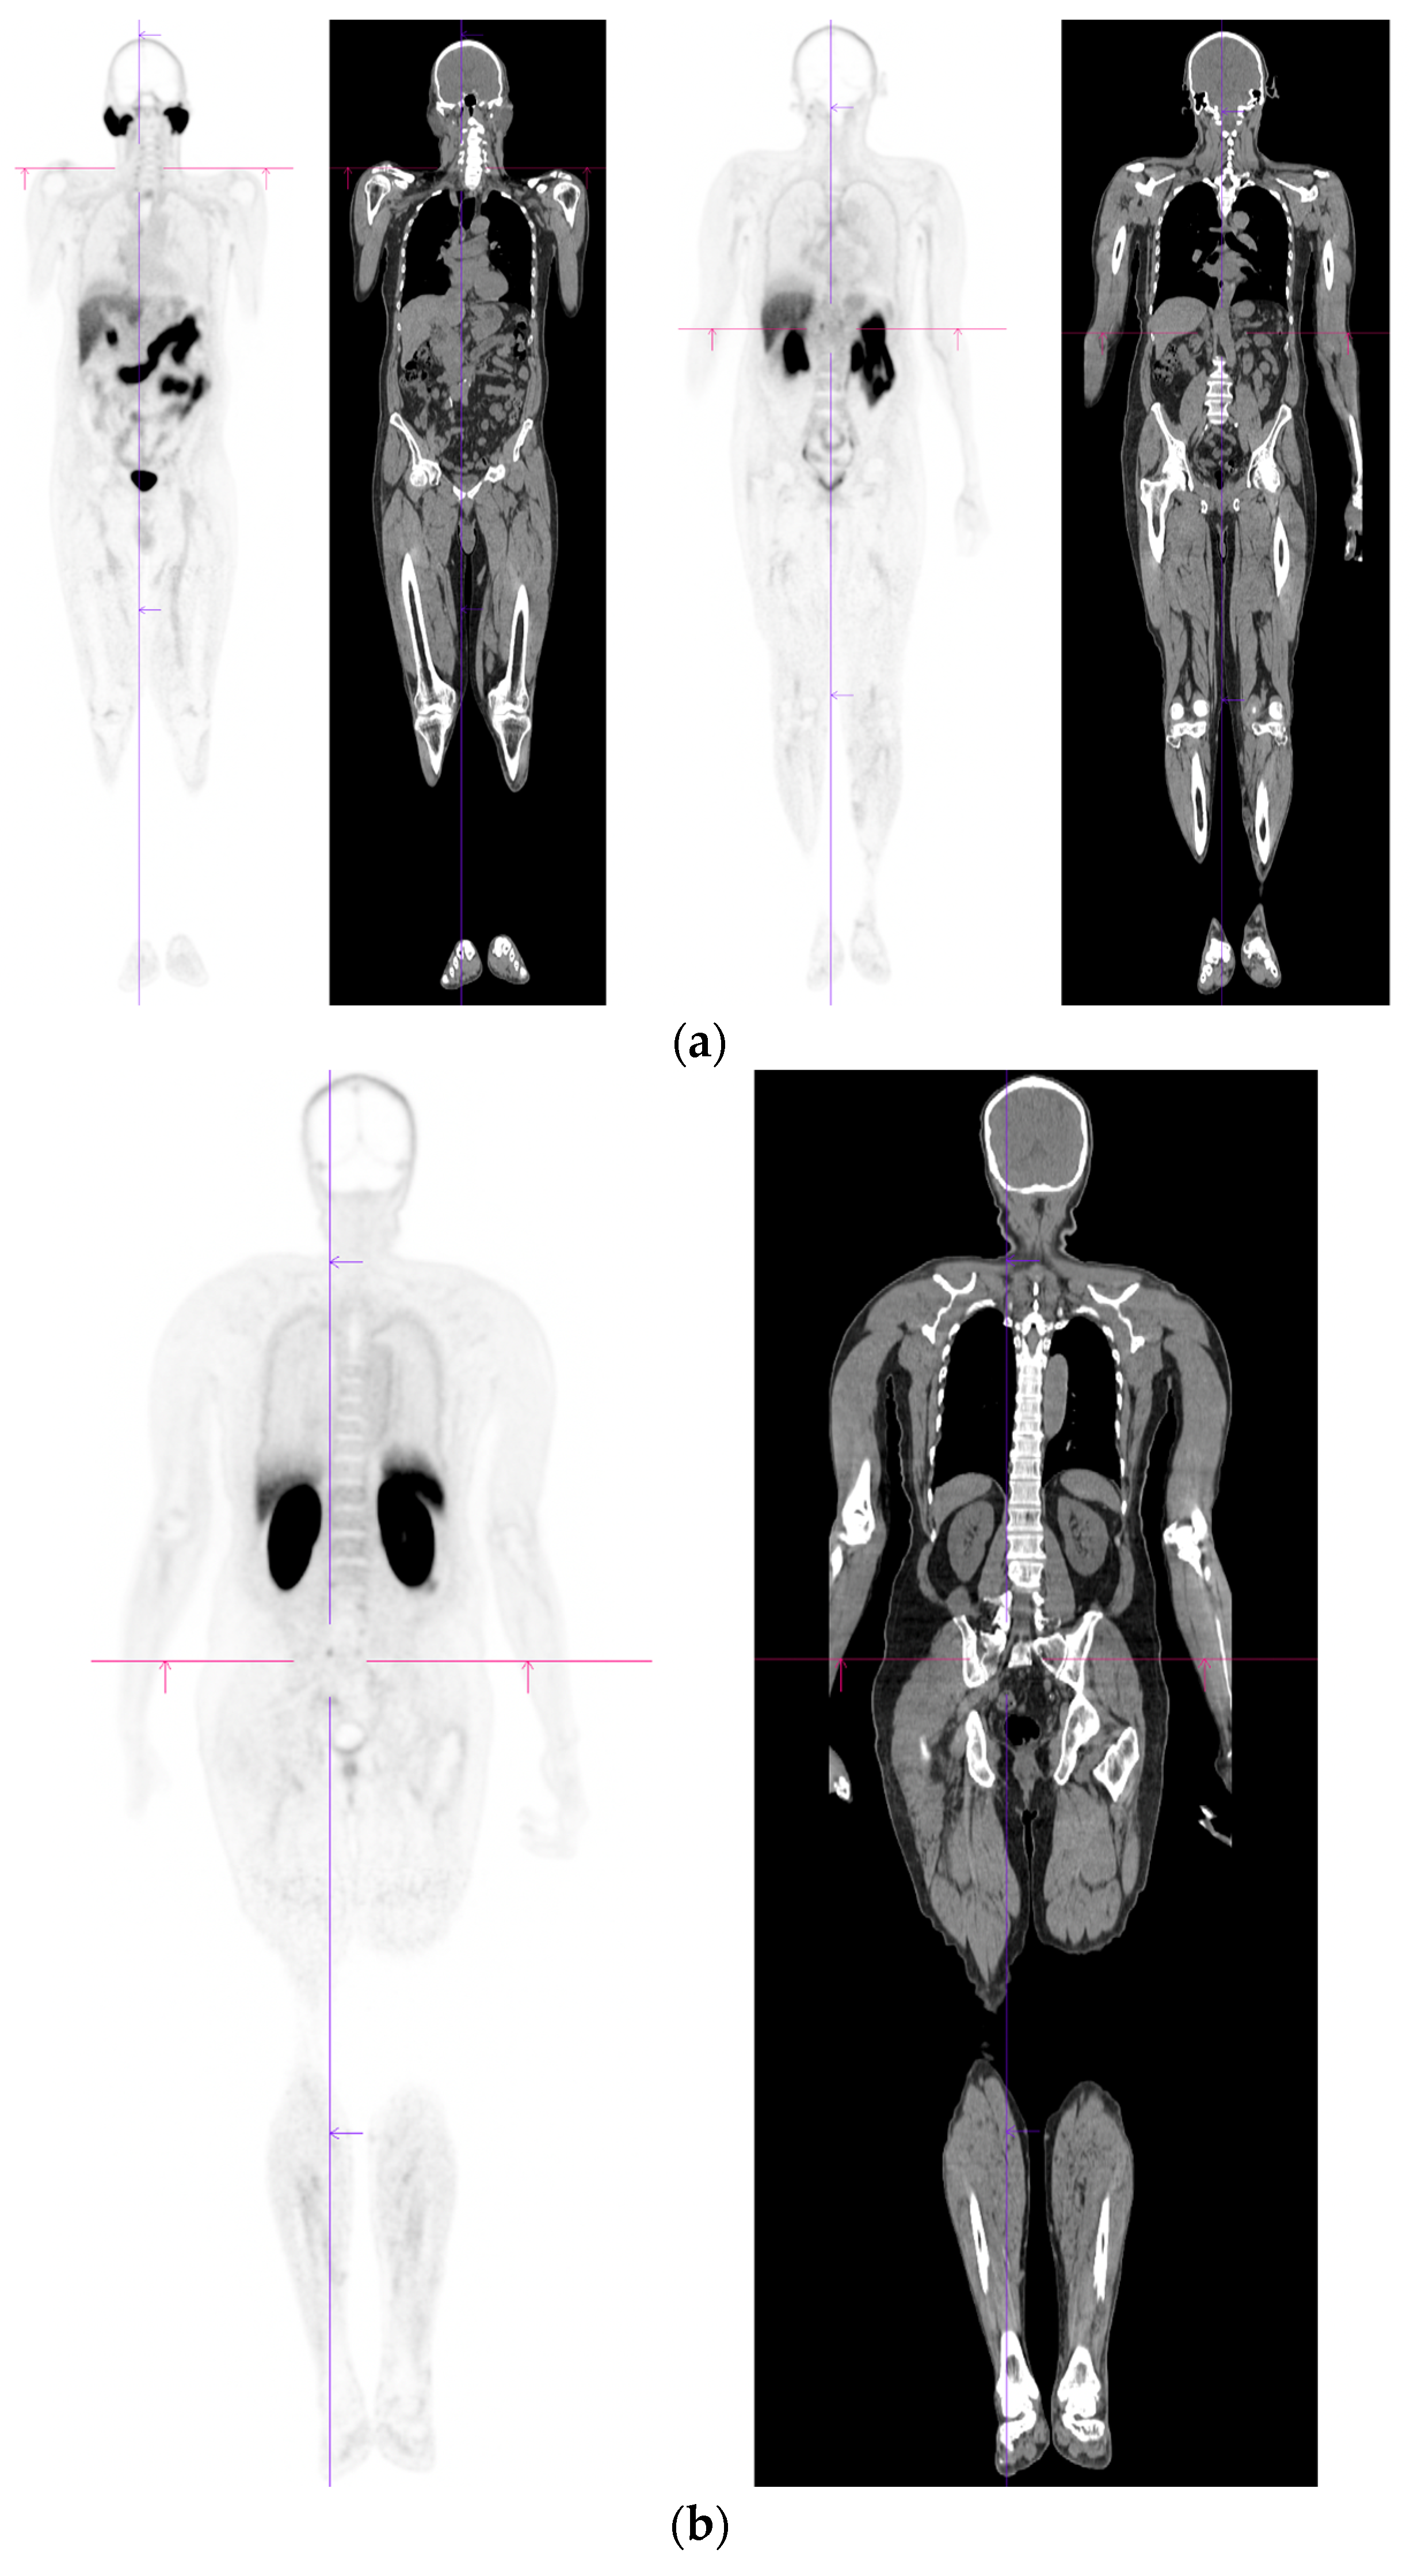

- Lawal, I.O.; Lengana, T.; Popoola, G.O.; Orunmuyi, A.T.; Kgatle, M.M.; Mokoala, K.M.G.; Sathekge, M.M. Pattern of Prostate Cancer Recurrence Assessed by 68Ga-PSMA-11 PET/CT in Men Treated with Primary Local Therapy. J. Clin. Med. 2021, 10, 3883. [Google Scholar] [CrossRef]

- Barbosa, F.G.; Queiroz, M.A.; Nunes, R.F.; Viana, P.C.C.; Marin, J.F.G.; Cerri, G.G.; Buchpiguel, C.A. Revisiting Prostate Cancer Recurrence with PSMA PET: Atlas of Typical and Atypical Patterns of Spread. Radiographics 2019, 39, 186–212. [Google Scholar] [CrossRef]